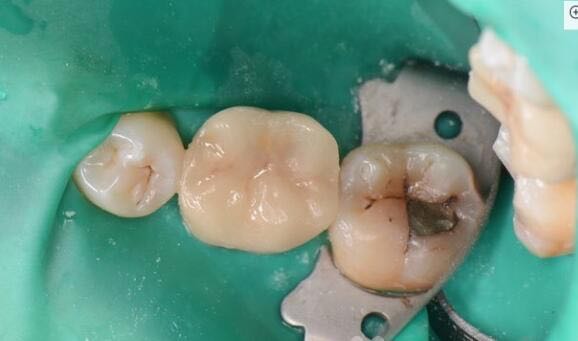

患者女性,自诉左下后牙咀嚼不适一个多月,食物嵌塞,来诊求治

检查:36远中临合洞,he面银汞充填物,X光见髓腔内有高密度影像,干髓术后,根尖无骨密度减低区

36牙中龋 36牙嵌体修复